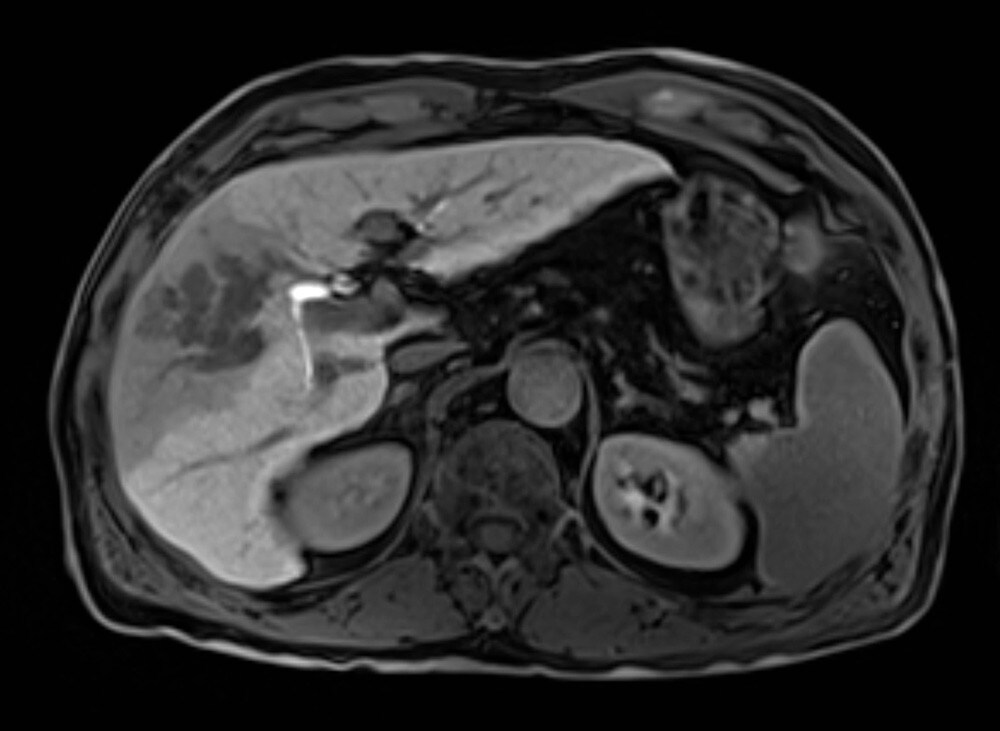

60歳代、男性、57kg、肝細胞癌

前医よりB型慢性肝炎に対して核酸アナログ投与し定期フォローを継続されていた.AFP上昇,腹部USでの画像異常を指摘され精査加療目的に当院紹介受診となり,EOB-MRIを施行した.

EOB-MRIの結果から門脈本幹までの腫瘍栓を伴う肝細胞癌と診断した.EOB-MRI肝細胞相で不均一高信号を呈する病変ではなく,均一低信号を呈しており複合免疫療法が奏効する可能性があると考えられた.Vp4の門脈腫瘍栓を伴う切除不能進行肝癌に対し複合免疫療法(Atezolizumab/Bevacizumab併用療法)を開始した.4コース終了後には門脈腫瘍栓一部残存を認めるも肝腫瘤は著明に縮小し,5コース終了後に根治切除術(肝右葉切除術+門脈血栓除去術)を施行した.術後は薬物療法の再開なく現在までの約14ヶ月無再発で経過観察継続中である.

本症例におけるEOB・プリモビスト造影MRIの役割について

EOB-MRIで門脈腫瘍栓を伴う肝細胞癌であること,不均一高信号を呈する病変で無いことを確認し複合免疫療法(Atezolizumab/Bevacizumab併用療法)を開始した.EOB-MRI肝細胞相は肝細胞癌におけるWnt/βカテニン変異のイメージングバイオマーカーとなることが知られており(Ueno A et al. J Hepatol 61:1080-1087,2014),不均一高信号な病変は複合免疫療法の治療効果が乏しい可能性が指摘されている(Sasaki et al. Cancers,14,827,2022).必ずしも治療奏効を保障するものでは無いが,本症例では肝細胞相で均一低信号を呈しており,複合免疫療法の治療効果が期待される症例であった.